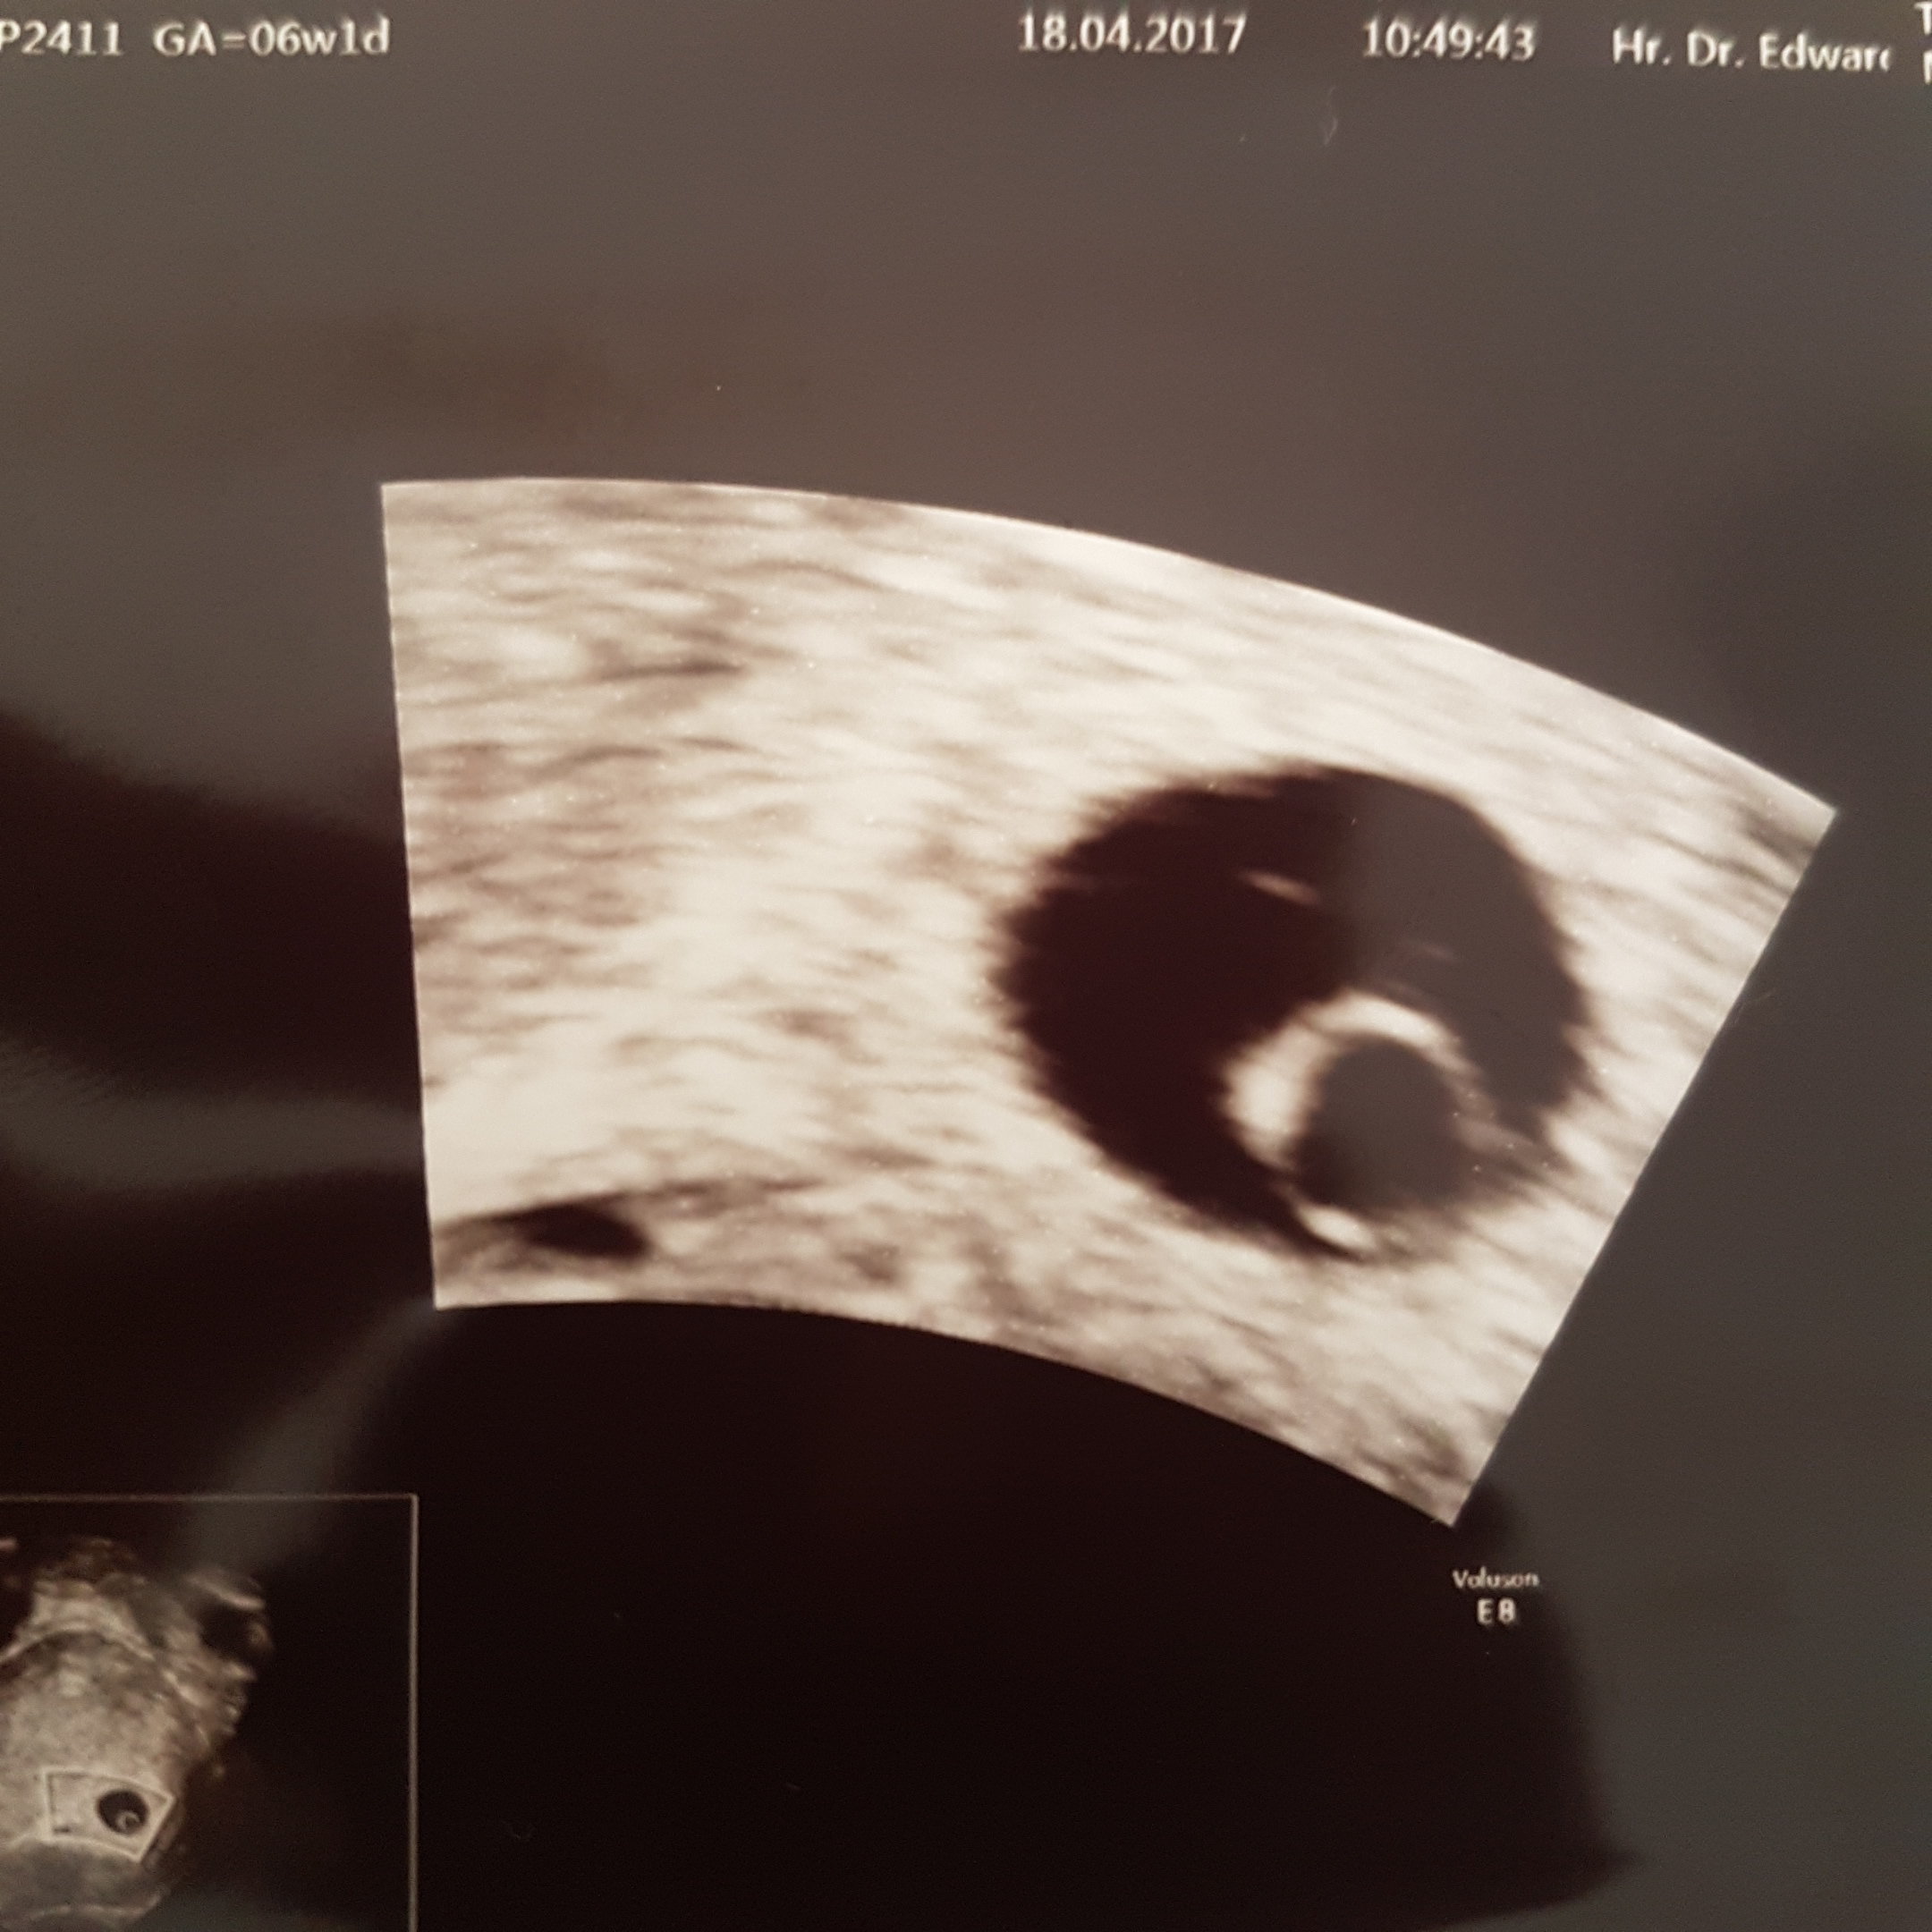

Zobacz załącznik 803058 6t 1d. Wszystko pasuje jak z om. Lekarz powiedział że wszystko jest ok. Następna wizyta za 3tyg.. Jestesmy szczęśliwi.

...........:::::::6tydz i 0dni:::::::::..........